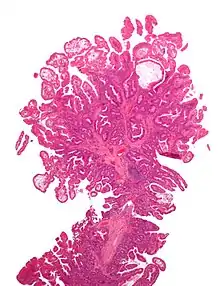

Tubulovillous adenoma 20% to 25%[15] 25–75% villous[14]

Villous adenoma 15%[16] to 40%[15] Over 75% villous[14]